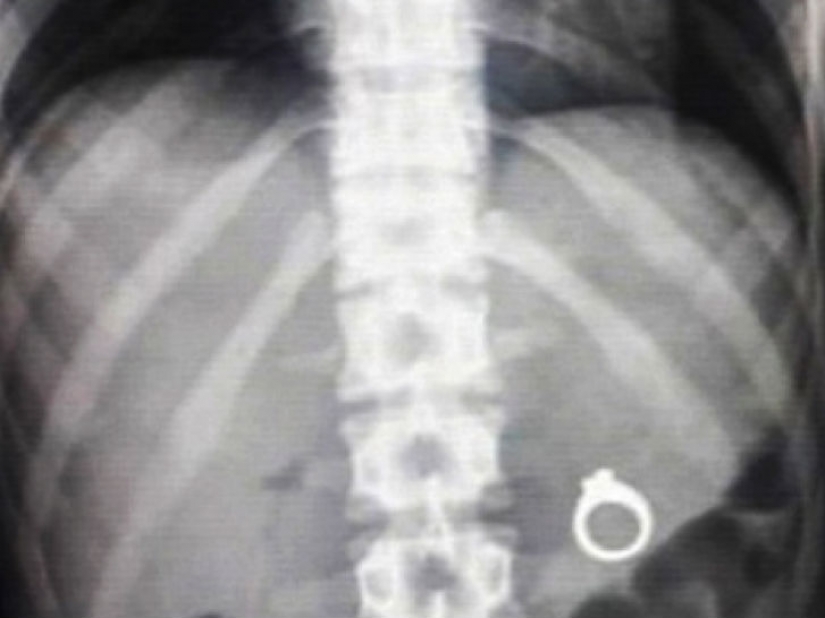

Muchos hombres quieren ser romántico y proponer a su novia en cierta manera inusual. Y muchos utilizan, por ejemplo, ir a ocultar que hay una sorpresa en forma de un anillo. Así, los hombres, hacer una oferta antes de que su novio decide probar este plato con una sorpresa.